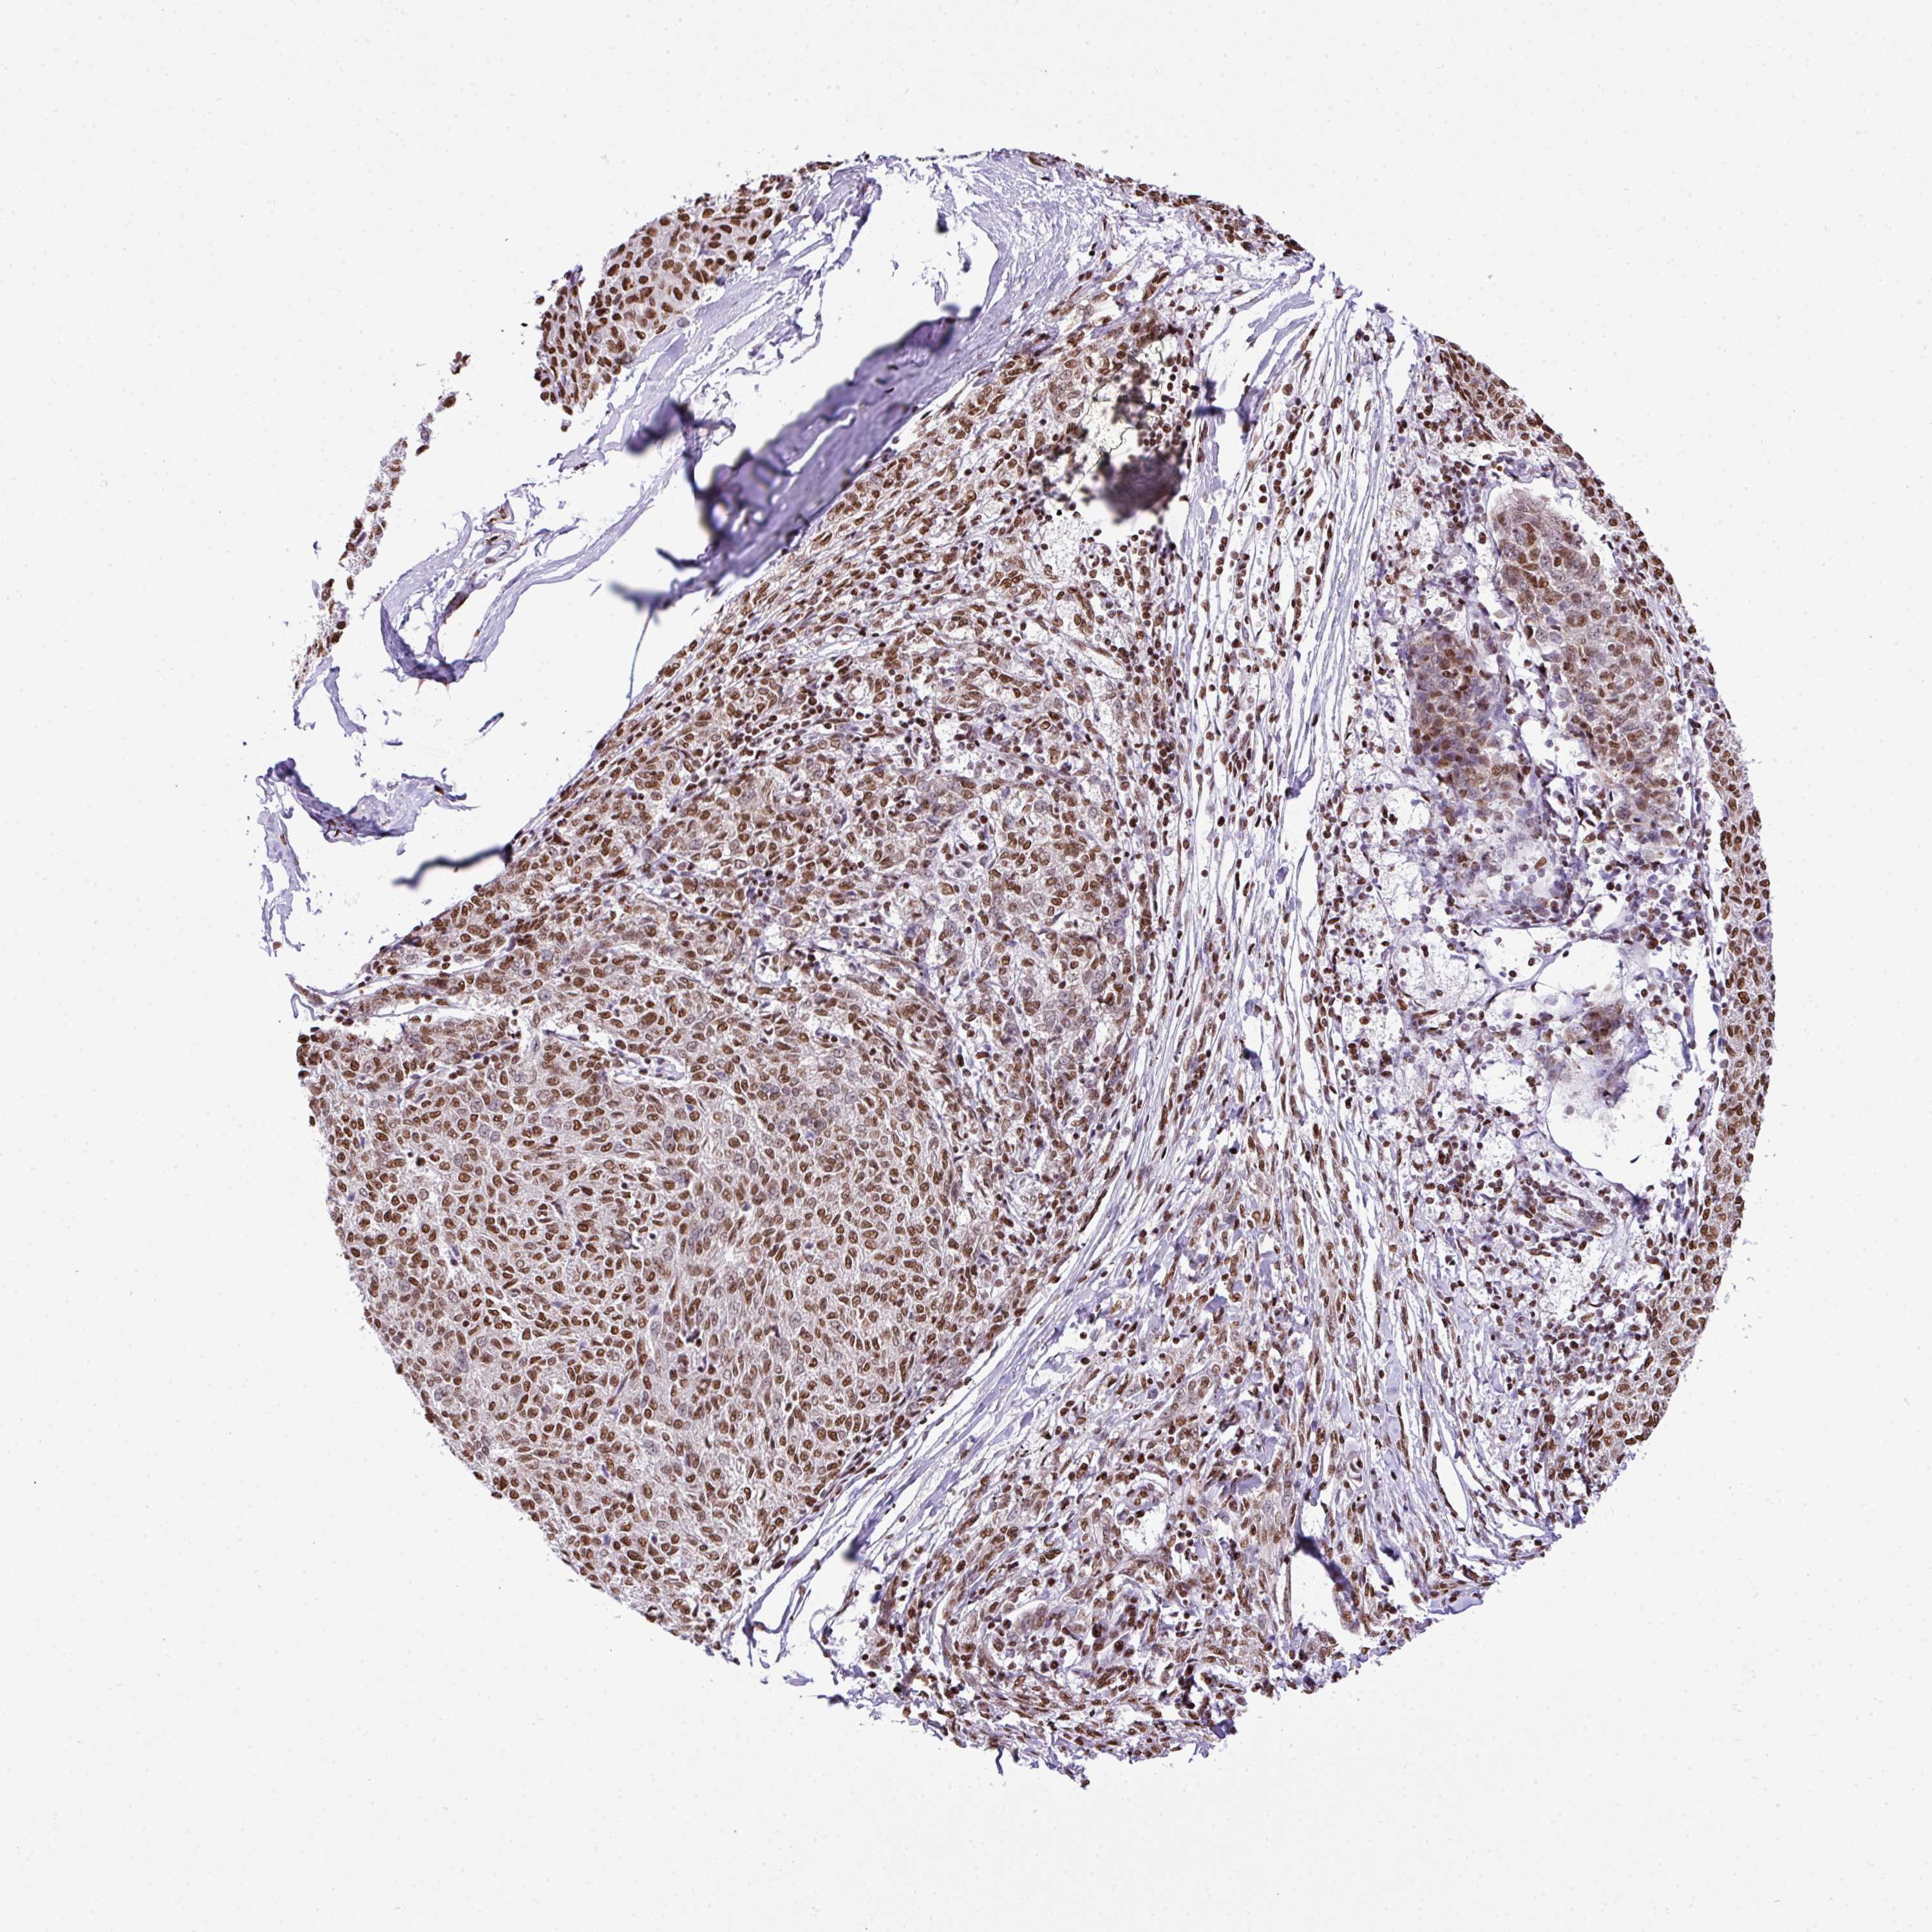

MELANOMA - Protein expressioni

A mouse-over function shows sample information and annotation data. Click on an image to view it in a full screen mode. Samples can be filtered based on level of antibody staining by selecting one or several of the following categories: high, medium, low and not detected. The assay and annotation is described here.

Note that samples used for immunohistochemistry by the Human Protein Atlas do not correspond to samples in the TCGA dataset.

Antibody stainingi

Antibody staining in the annotated cell types in the current human tissue is reported as not detected, low, medium, or high, based on conventional immunohistochemistry profiling in selected tissues. This score is based on the combination of the staining intensity and fraction of stained cells.

Each image is clickable and will lead to virtual microscopy that enables deeper exploration of all samples and also displays staining intensity scores, fraction scores and subcellular localization as well as patient and tissue information for each sample.

Antibody HPA053883

Staining

High

Medium

Low

Not detected

Intensity

Strong

Moderate

Weak

Negative

Quantity

>75%

75%-25%

<25%

None

Location

Nuclear

Cytoplasmic/membranous

Cytoplasmic/membranous,nuclear

Malignant melanoma, Metastatic site